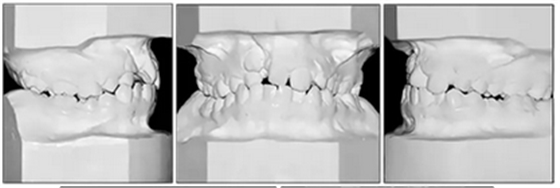

咬合關(guān)系:右側(cè)磨牙有II類關(guān)系傾向,尖牙關(guān)系II類;左側(cè)磨牙關(guān)系完全I(xiàn)I類,尖牙關(guān)系I類。上頜雙側(cè)反合,中線稍有偏離。覆合、覆蓋減少。上頜中切牙向腭裂側(cè)旋轉(zhuǎn),上頜右側(cè)尖牙頰側(cè)異位萌出,雙側(cè)乳尖牙仍存在?;颊呱项M弓嚴(yán)重?fù)頂D(擁擠度約10mm),下頜弓輕度擁擠4mm(擁擠度約4mm)(圖1 ;圖2)。牙周檢查良好。

頭部側(cè)位片測量顯示骨性I類錯合畸形(ANB,3.5°),垂直生長模式(SN / GoMe,39°),上頜中切牙后傾(1 / SN,94°)和下頜中切牙前傾(IMPA,100 °)(圖3)。